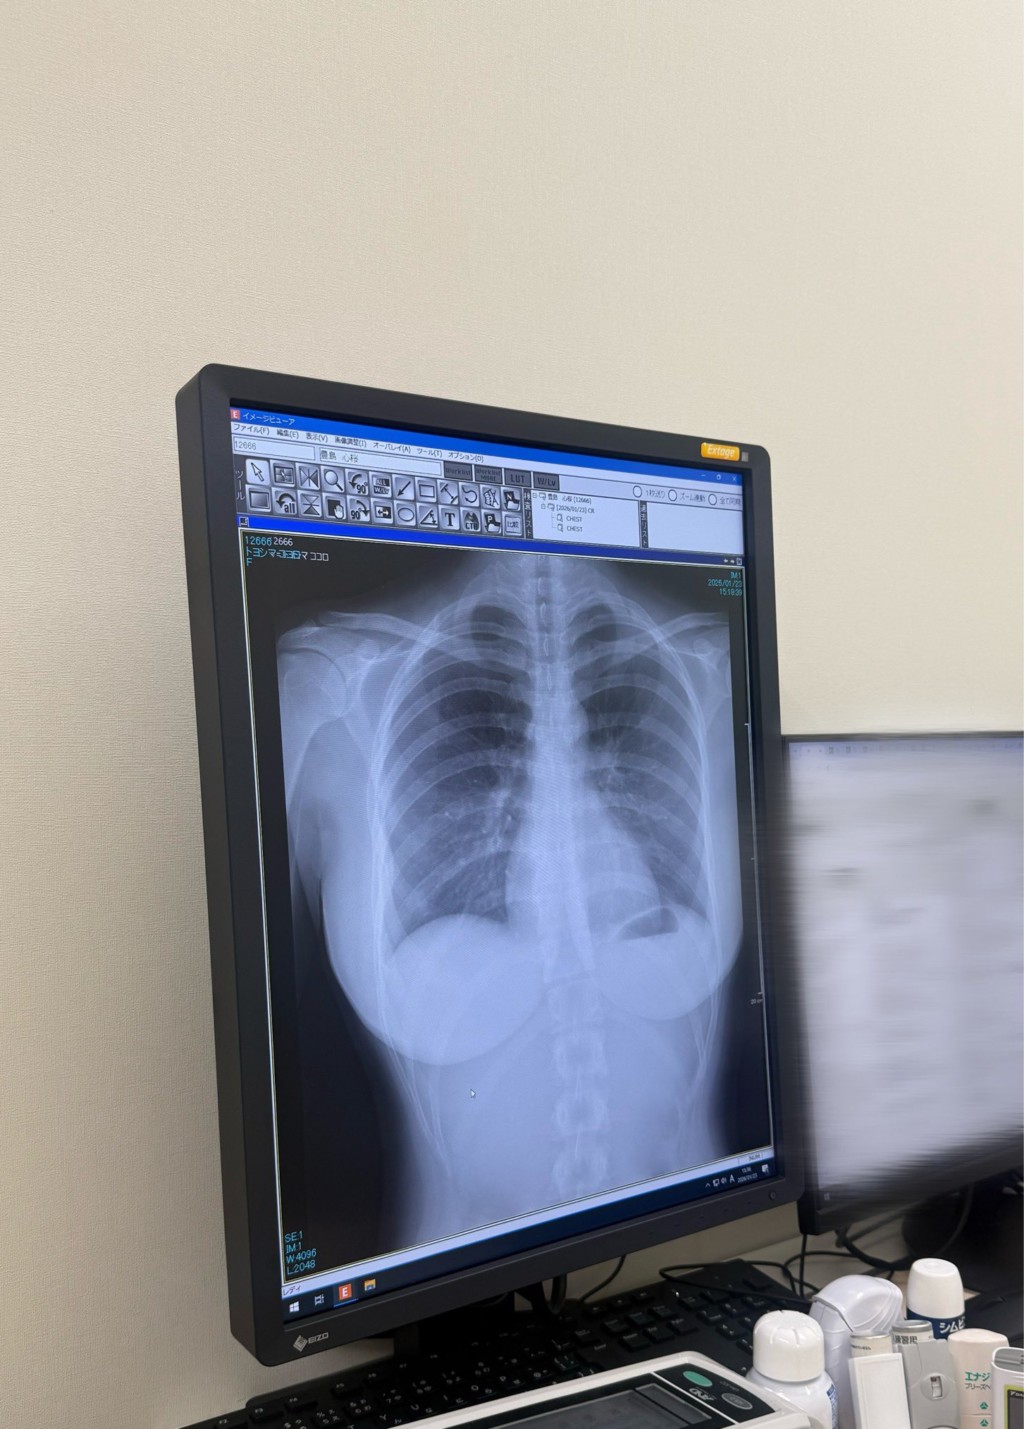

23日,豐島心櫻在社群平台X上曬出了一張胸腔X光片,並炫耀「我的肺很乾淨」,原本只是單純要向粉絲回報身體很健康,誰知影像曝光後卻意外引爆話題,留言區幾乎被玩笑與驚呼淹沒。

「這形狀真不錯」、「非常漂亮的肺」、「第一次看到這麼驚人的X光片、太刺激了」、「仔細看了一下,形狀真漂亮」、「肺在哪?」、「寫真偶像的X光片好刺激」。原來,豐島心櫻的X光照不僅顯現了清楚的肺部,連她的身型輪廓也跟著一覽無遺,不過有熱心網友也發現,豐島心櫻似乎有脊椎側彎的問題,提醒平時要多多注意姿勢。